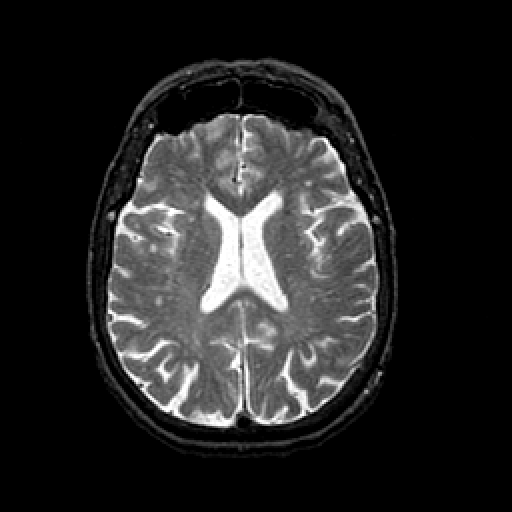

T2-weighted structural MR: Slice 32

Slice 32